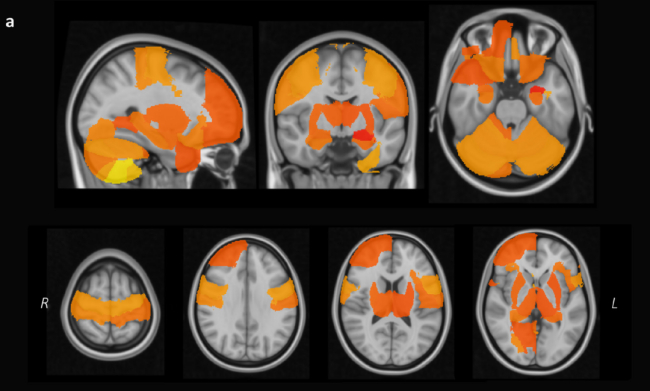

更为深刻的是,与每晚睡眠充足6~8小时的人相比,睡眠时间少于6小时的人,大脑体积更小,比如右侧伏核体积减小2.0%至右前极体积减小0.5%。

睡眠 6~8 小时的人大脑体积更大。图片来自参考文献[9]